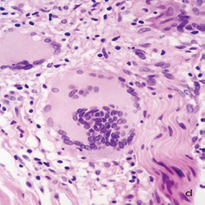

The infiltrates surrounded several neural bundles, which had dissociated perineurium (Figure 3,4).

Figure 3a A nerve in the center of the figure has dispersed perineurium and is surrounded by a giant cell. The peripheral infiltrate has many giant cells with numerous nuclei, lymphocytes and eosinophils.

Figure 3b These nerves (lower right B) have no defined perineurium and are surrounded by diffuse infiltrate of macrophages, giant cells, lymphocytes and eosinophils.

Figure 3c These nerves have no defined perineurium and are surrounded by diffuse infiltrate of macrophages, giant cells, lymphocytes and eosinophils. Vacuolated macrophages seem to be endoneural.

Figure 3d This nerve does not show perineurium and is surrounded by prominent giant cells, but looks well preserved. A-D: HE. A, B: 16 X. C, D: 40 X.

Some giant cells and macrophages touched the nerve or penetrate the endoneurium and distorted neural architecture (Figures 3,4). Other cutaneous nerves were located at the center of the infiltrate and looked well preserved (Figure 5).